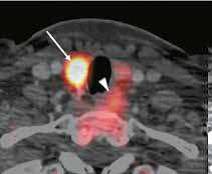

С 2020 по 2022 годы: «Изучение механизмов повреждения сердечно-сосудистой системы при гипо- и гиперпаратиреозе с целью разработки комплексного персонифицированного подхода обследования и лечения». В рамках данной работы проведен анализ встречаемости сердечно-сосудистой патологии и ее спектра у больных первичным гиперпаратиреозом. Установлены особенности ремоделирования сердца и сосудов в условиях гиперкальциемии и изменения после паратиреоидэктомии. Внедрено использование метода ПЭТ/ КТ с 11С-метионином и холином для диагностики эктопированных и множественных аденом околощитовидных желез. Установлено,что чувствительность и специфичность ПЭТ-КТ при диагностикеаденом околощитовидных желез выше, чем у стандартных методов исследования (МСКТ, сцинтиграфия и УЗИ). Дополнительно наблюдение за больными гипопаратиреозом (гипоПТ) показало, что качество жизни пациентов значимо снижено как со стороны физического, так и со стороны ментального здоровья. После коррекции терапии показатели качества жизни значимо вырастают. Проведен анализ встречаемости ССЗ у больных гипоПТ. Было показано, что у больных хирургическим гипоПТ преобладает артериальная гипертензия, а у больных нехирургическим гипоПТ преобладают нарушения ритма и проводимости.

| Аденома правой нижней околощитовидной железы и интратиреоидное расположение аденомы левой нижней околощитовидной железы по данным ПЭТ-КТ с 11С-МЕТ. | |